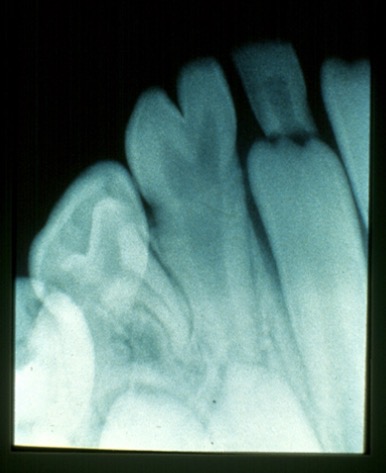

What is this condition?

Tetracycline stain

-Endogenous/intrinsic stain